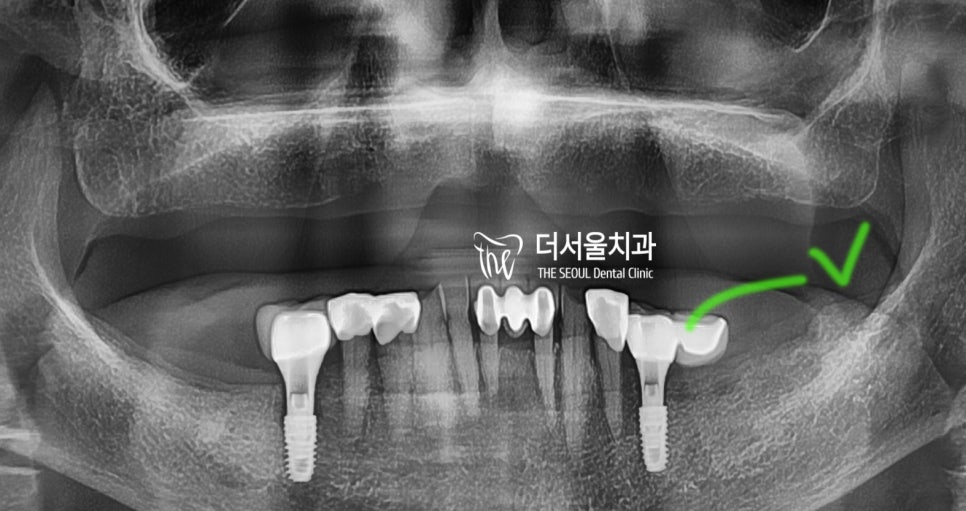

이후, 2개월뒤에 최종 보철까지

연결을 해드렸고

체크를 해둔 곳을 보면은, 한 쪽이

허공에 떠 있는 것을 보실 수 있죠?

바로 cantilever bridge 라는겁니다.